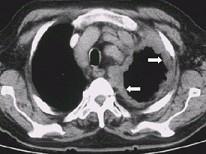

问题 男,54岁,胸痛1月伴加重,CT如图,应考虑为 ( )

选项 A.淋巴瘤 B.左侧胸膜转移瘤 C.左侧胸膜间皮瘤 D.左侧胸膜增厚 E.左上肺不张伴胸膜增厚

答案 C